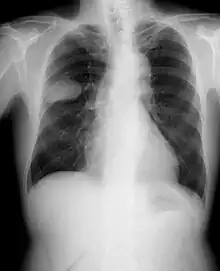

Le cancer du poumon peut être vu sur les radiographies thoraciques et le scanner. Le diagnostic est confirmé par une biopsie. Ceci se fait généralement par bronchoscopie, ou par biopsie guidée par scanner. Le traitement et le pronostic dépendent du type histologique du cancer, de son stade (degré de dissémination), et de l'état général de santé du patient.

La radiographie thoracique est la première mesure à prendre si un patient se plaint de symptômes pouvant suggérer un cancer du poumon. Ceci peut révéler une masse évidente, un élargissement du médiastin (qui suggère une extension aux ganglions lymphatiques qui s'y trouvent), une atélectasie (affaissement), une inflammation (pneumonie) ou un épanchement pleural. En l'absence de signes radiographiques, mais si les soupçons sont élevés (par exemple, un gros fumeur avec hémoptysie), une bronchoscopie ou un scanner peuvent donner l'information nécessaire. La bronchoscopie ou la biopsie guidée par scanner sont souvent utilisées pour identifier le type de tumeur[3].